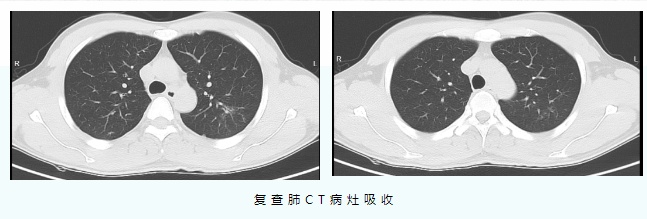

经过中西医结合对症治疗10天后,肺部CT等检查提示,患者的肺炎较之前明显吸收,目前已好转出院。